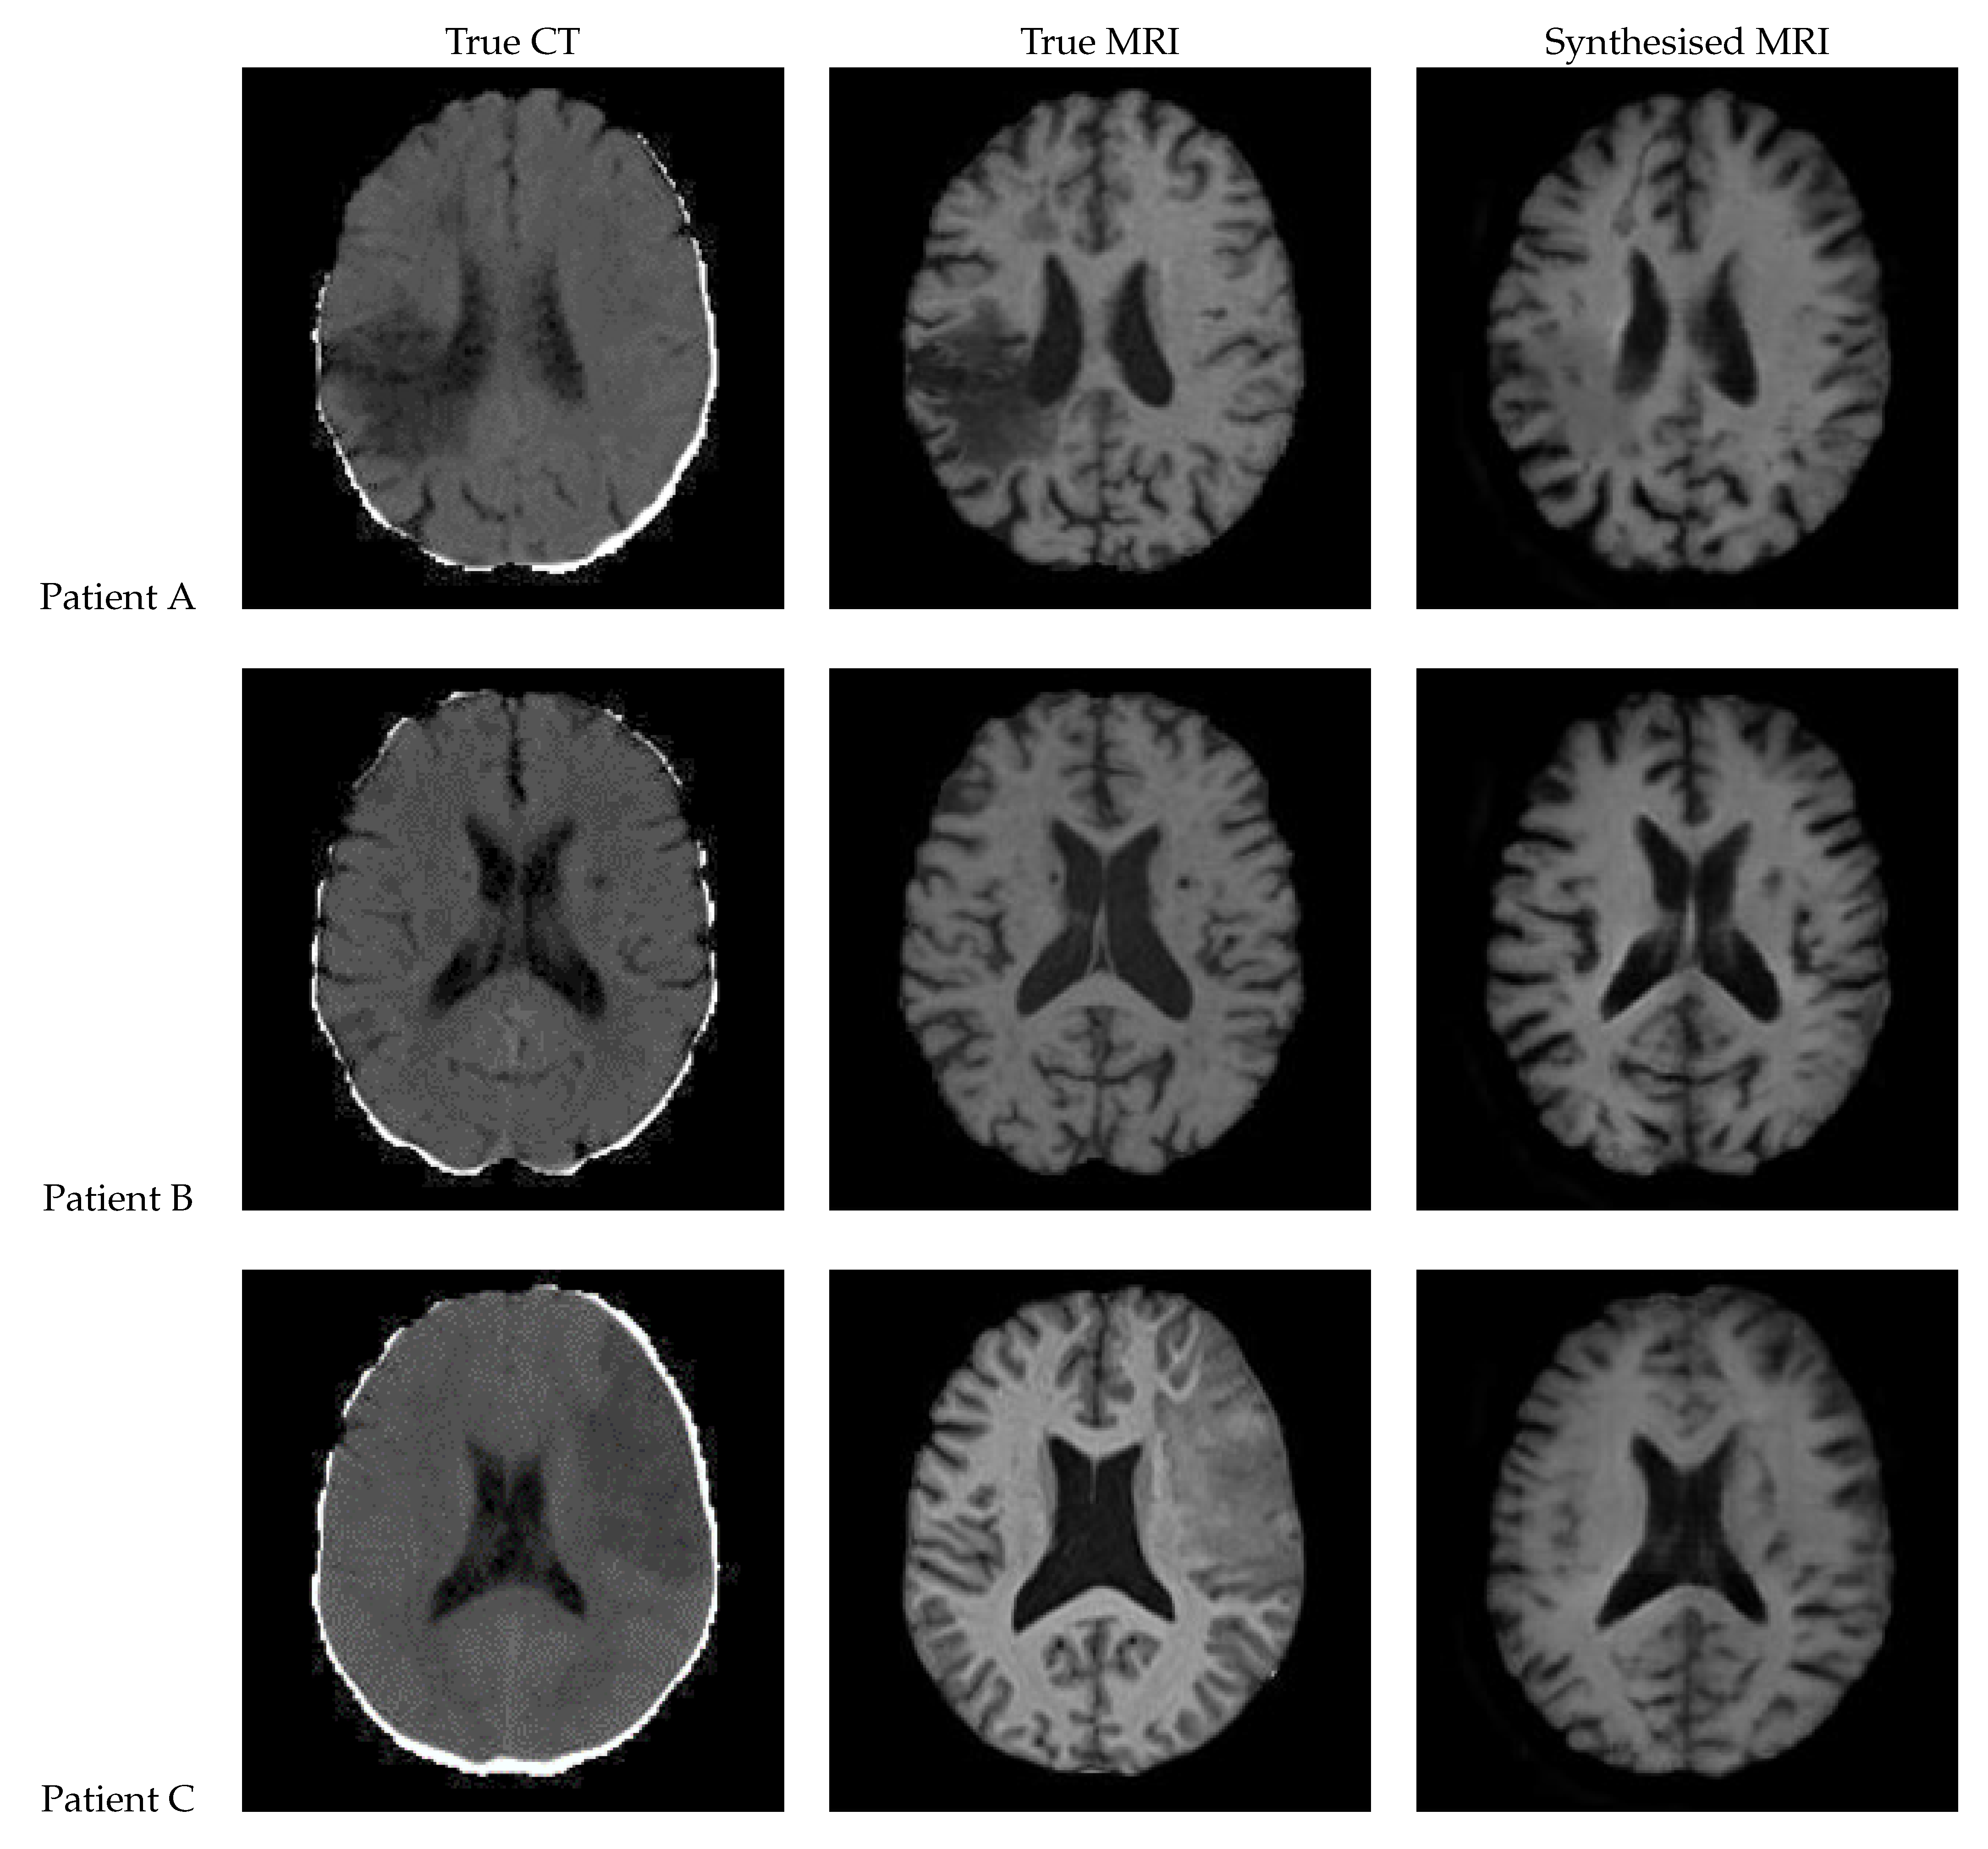

Figure 14 presents the results of a patch-based 3D UNet. The edges of the patches are clearly visible, and the patches do align smoothly but still differ in intensity. The lesion can be clearly seen in the synthetic image for Patient A, appearing on both of the left-hand side patches. It is difficult to tell whether the lesion is present for Patient C, although the general region appears hypointense.

Figure 14. Axial slices of CT Scans (Left), True MRIs (Centre), and Synthetic MRIs generated by Patch Based UNet (Right).